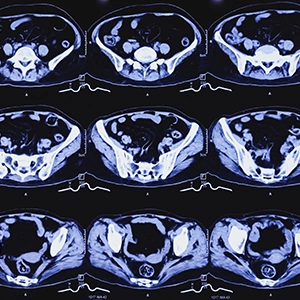

A virtual colonoscopy uses a CT scanner to take high-resolution images of your colon and rectum. These images are captured at various angles, called slices, to create a 3D view of your large intestine, similar to what your doctor would see during your traditional colonoscopy.

After your scan, one of our board-certified radiologists will review the images and look for any signs of concern, such as polyps, inflammation, and other abnormalities.